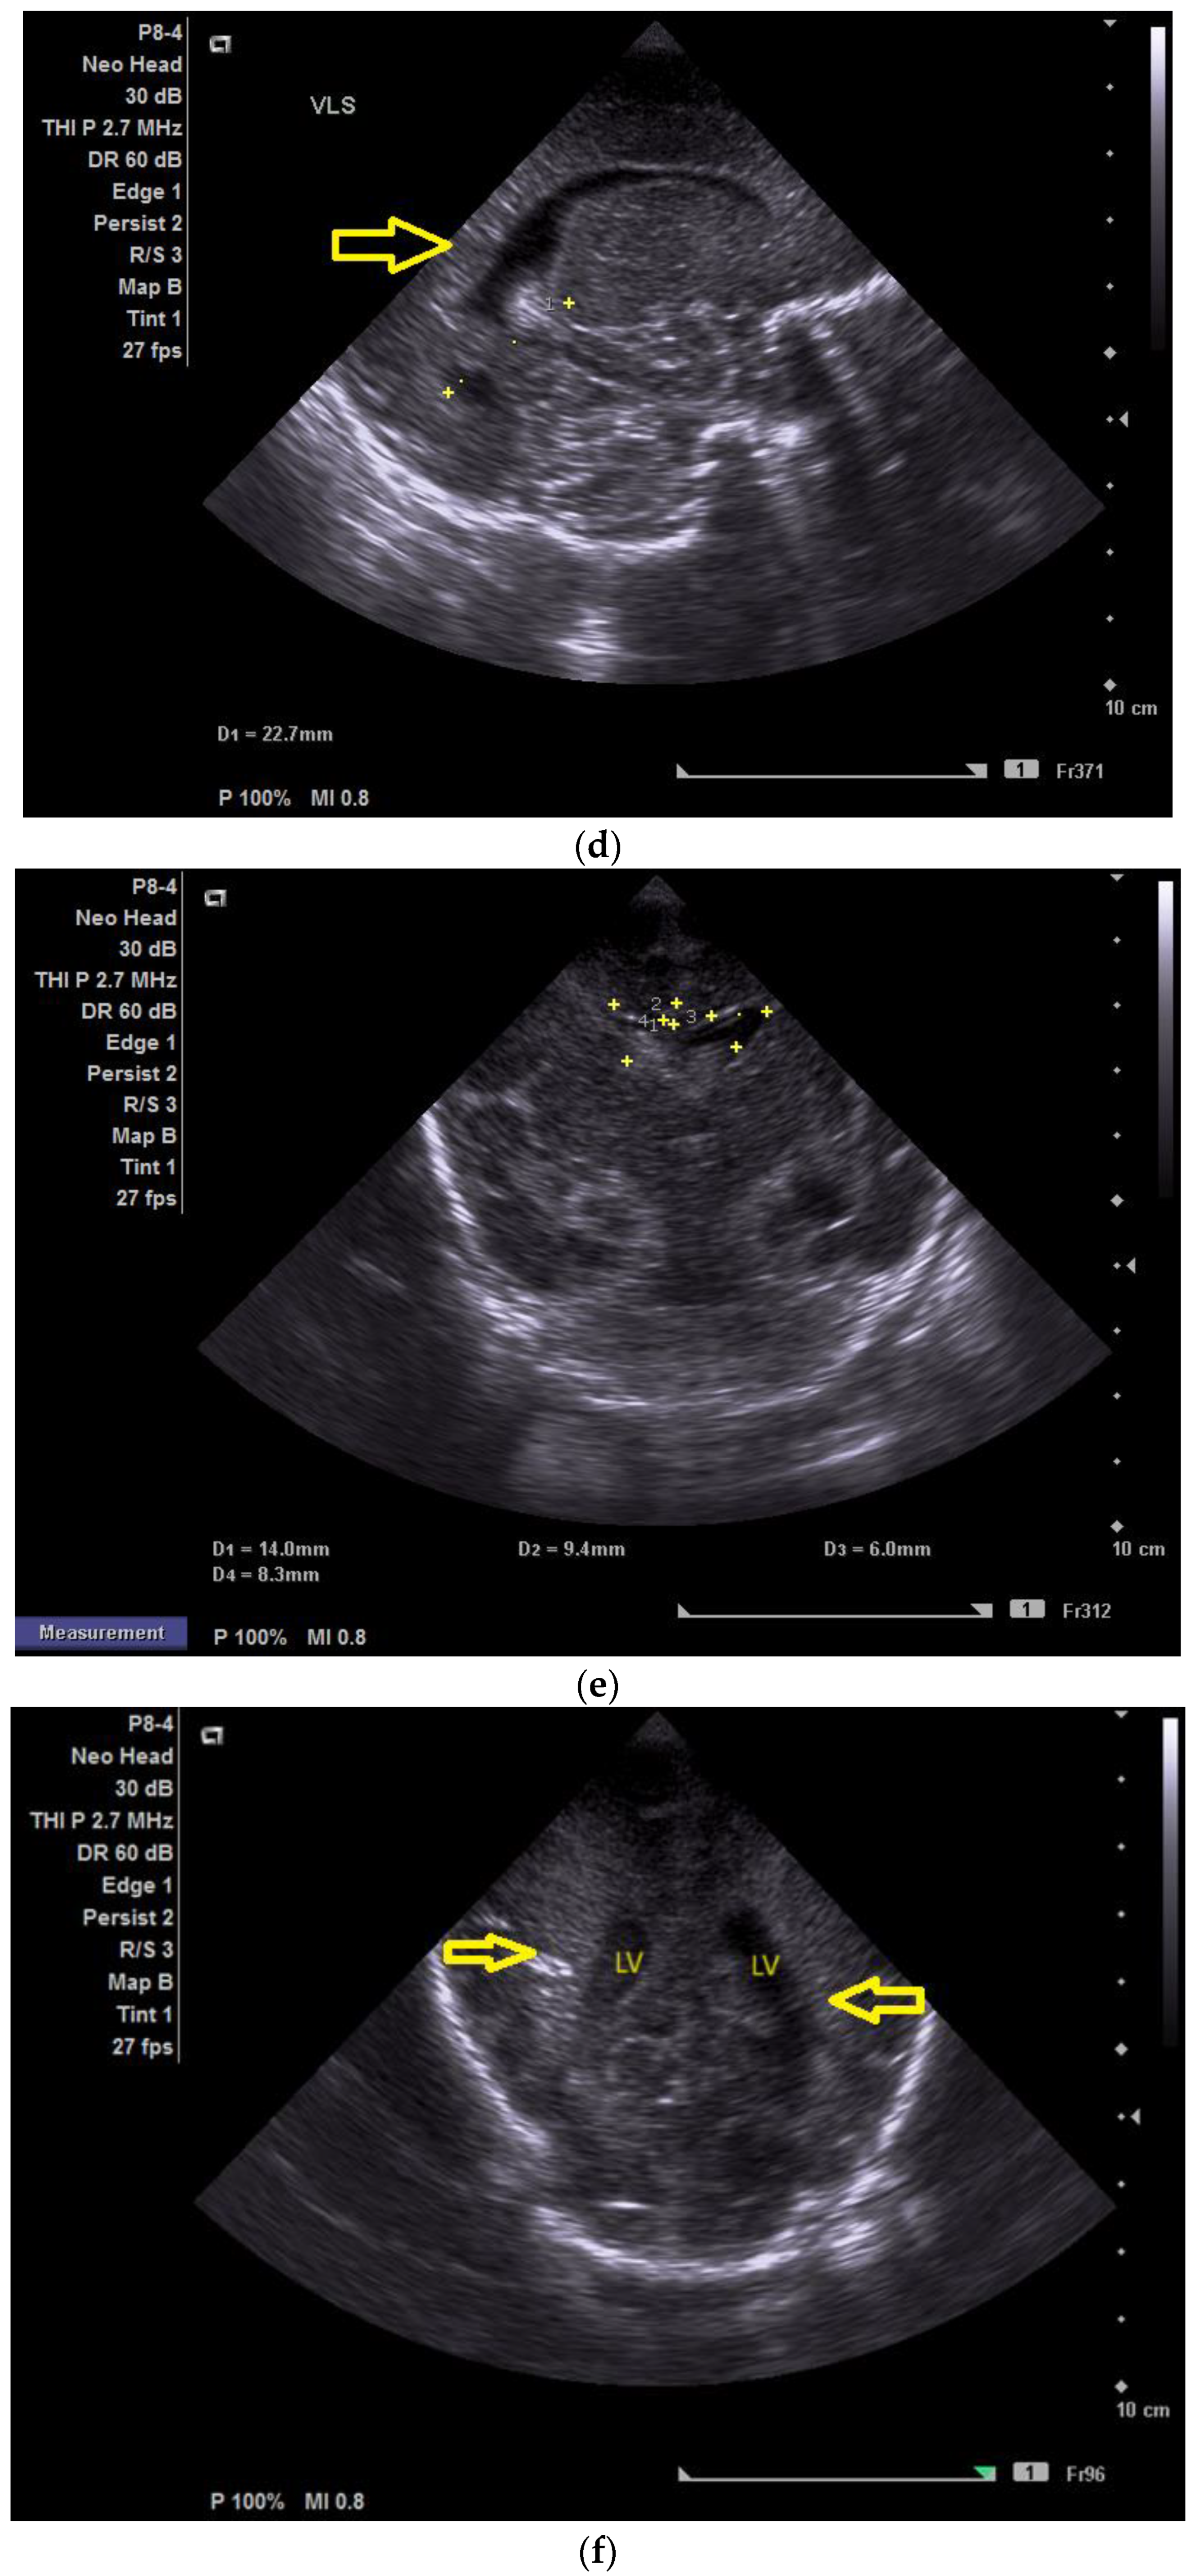

Case 3 involved a preterm newborn (33 3/7 weeks of gestation) with antenatal lateral ventricle asymmetry, for which a left ventricular hyperechoic image with the fetal MRI was performed at 28 weeks of gestation, born from a mother with recurrent UTIs (urinary tract infections) with E. Coli who was extracted through C-section and required resuscitation at birth (T-piece resuscitator). A nasal CPAP was provided for almost 36 h and antibiotic therapy was initiated (Vancomycin® and Cefotaxime® for three days).

The first CUS was performed 24 h after birth and showed dilation of the third and fourth lateral ventricles, enlargement of the Sylvius aqueduct, and the presence of an arachnoid cyst (Figure 3a–e).

Figure 3.

(a) Cranial ultrasound. Coronal view. Enlargement of the lateral ventricles with hyperechoic and third ventricle dilation. D1, D2—Levine index measurement. D3, D4—anterior horn width measurement. D5—third ventricle (personal image collection). (b) Cranial ultrasound. Sagittal view. Up—left ventricle. D1, D2—lateral ventricle measurements and thalamo-occipital horn width. Down—right ventricle. D1, D2—lateral ventricle measurements and thalamo-occipital horn width (personal image collection). (c) Cranial ultrasound. Sagittal view. Up—enlargement of the third and fourth ventricles. Measurements of the ventricles. Down—measurement of the resistive index (RI) performed on the anterior cerebral artery (ACA) using Doppler flow measurements. RI—0.74 (personal image collection). (d) Cranial ultrasound. Transtemporal view. Yellow arrow—enlargement of the Sylvian aqueduct (personal image collection). (e) Cranial ultrasound. Sagittal view. Yellow arrow—arachnoid cyst posterior to the third ventricle (personal image collection). (f) Cranial ultrasound. Coronal view. Lateral ventricles and third ventricle enlargement. D1, D2—Levine index measurement. D3, D6—right lateral ventricle measurement (anterior horn width). D4, D5—left lateral ventricle measurement (anterior horn width) (personal image collection). (g) Cranial ultrasound. Sagittal view. Left—left ventricle. D1—thalamo-occipital distance measurement. Right—right ventricle. D2—thalamo-occipital distance measurement (personal image collection). (h) Cranial ultrasound. Coronal view. Up—orange arrow—third ventricle. Red arrow—fourth ventricles. Yellow arrow—arachnoid cyst. Down—resistive index measured on the anterior cerebral artery. RI—0.79 (personal image collection). (i) Cranial ultrasound. Transversal view. Up—RI precompression value on the middle cerebral artery performed with Doppler examination. RI—68. Down—RI post-compression value on the middle cerebral artery performed with Doppler examination. RI—0.79 (personal image collection). (j) Cranial ultrasound. Up—coronal view. L1, L2—Levine index measurement of the lateral ventricles. Down—sagittal view. L1, L2—measurement of the thalamo-occipital distance (personal image collection). (k) Cranial ultrasound. Sagittal view. L1, L2—measurement of the third ventricle. L3, L4—measurement of the fourth ventricle. L5, L6—measurement of the arachnoid cyst (personal image collection). (l). Head circumference-for-age. “X” symbols represent the measurements performed from birth and follow-up examinations. Head circumference was still under the curve during follow-up examinations (personal image collection) [28].

The CUS examination performed at 48 h after birth showed increases in the diameters of all ventricles. The resistive index presented an increase as well. The bregmatic fontanelle started bulging. The dimensions of the Sylvian aqueduct were not modified (Figure 3f–h).

The CUS examinations performed at four days and seven days after birth showed stabilization regarding the values of the diameters. The pre- and post-compression values of the resistive index of the middle cerebral artery showed a delta-RI of 0.11 (pre—0.68, post—0.79, Figure 3i).

After discharge, at three weeks after birth (follow-up examination), the ventricle measurements showed wider ventricles and the arachnoid cyst was still present (Figure 3j,k).

The next follow-up examination performed a week later showed a delta-RI of 0.12 and an increase in the cranial perimeter (+ one cm since the last follow-up).

At 12 weeks of life (five week corrected age), ventricle dilations were still present. Neurological examinations showed axial and limb hypotonia. The general movement examination showed a poor repertoire with a General Movement Optimality Score (GMOS) of 19. At 18 weeks of life (11 week corrected age), the neurological exam revealed that the infant presented plagiocephaly and could keep eye contact, and during the traction-to-sit maneuver showed hypotonia of the neck muscles. In the prone position, the infant was unable to hold the head up. The passive tone assessment showed the “scarf sign”, with the elbow at the midline bilaterally and a popliteal angle of 90° on the right and 110° on the left. Deep tendon reflexes were present. The general movement (GM) assessment revealed absent fidgety movements, with a Motor Optimality Score (MOS) of 13.